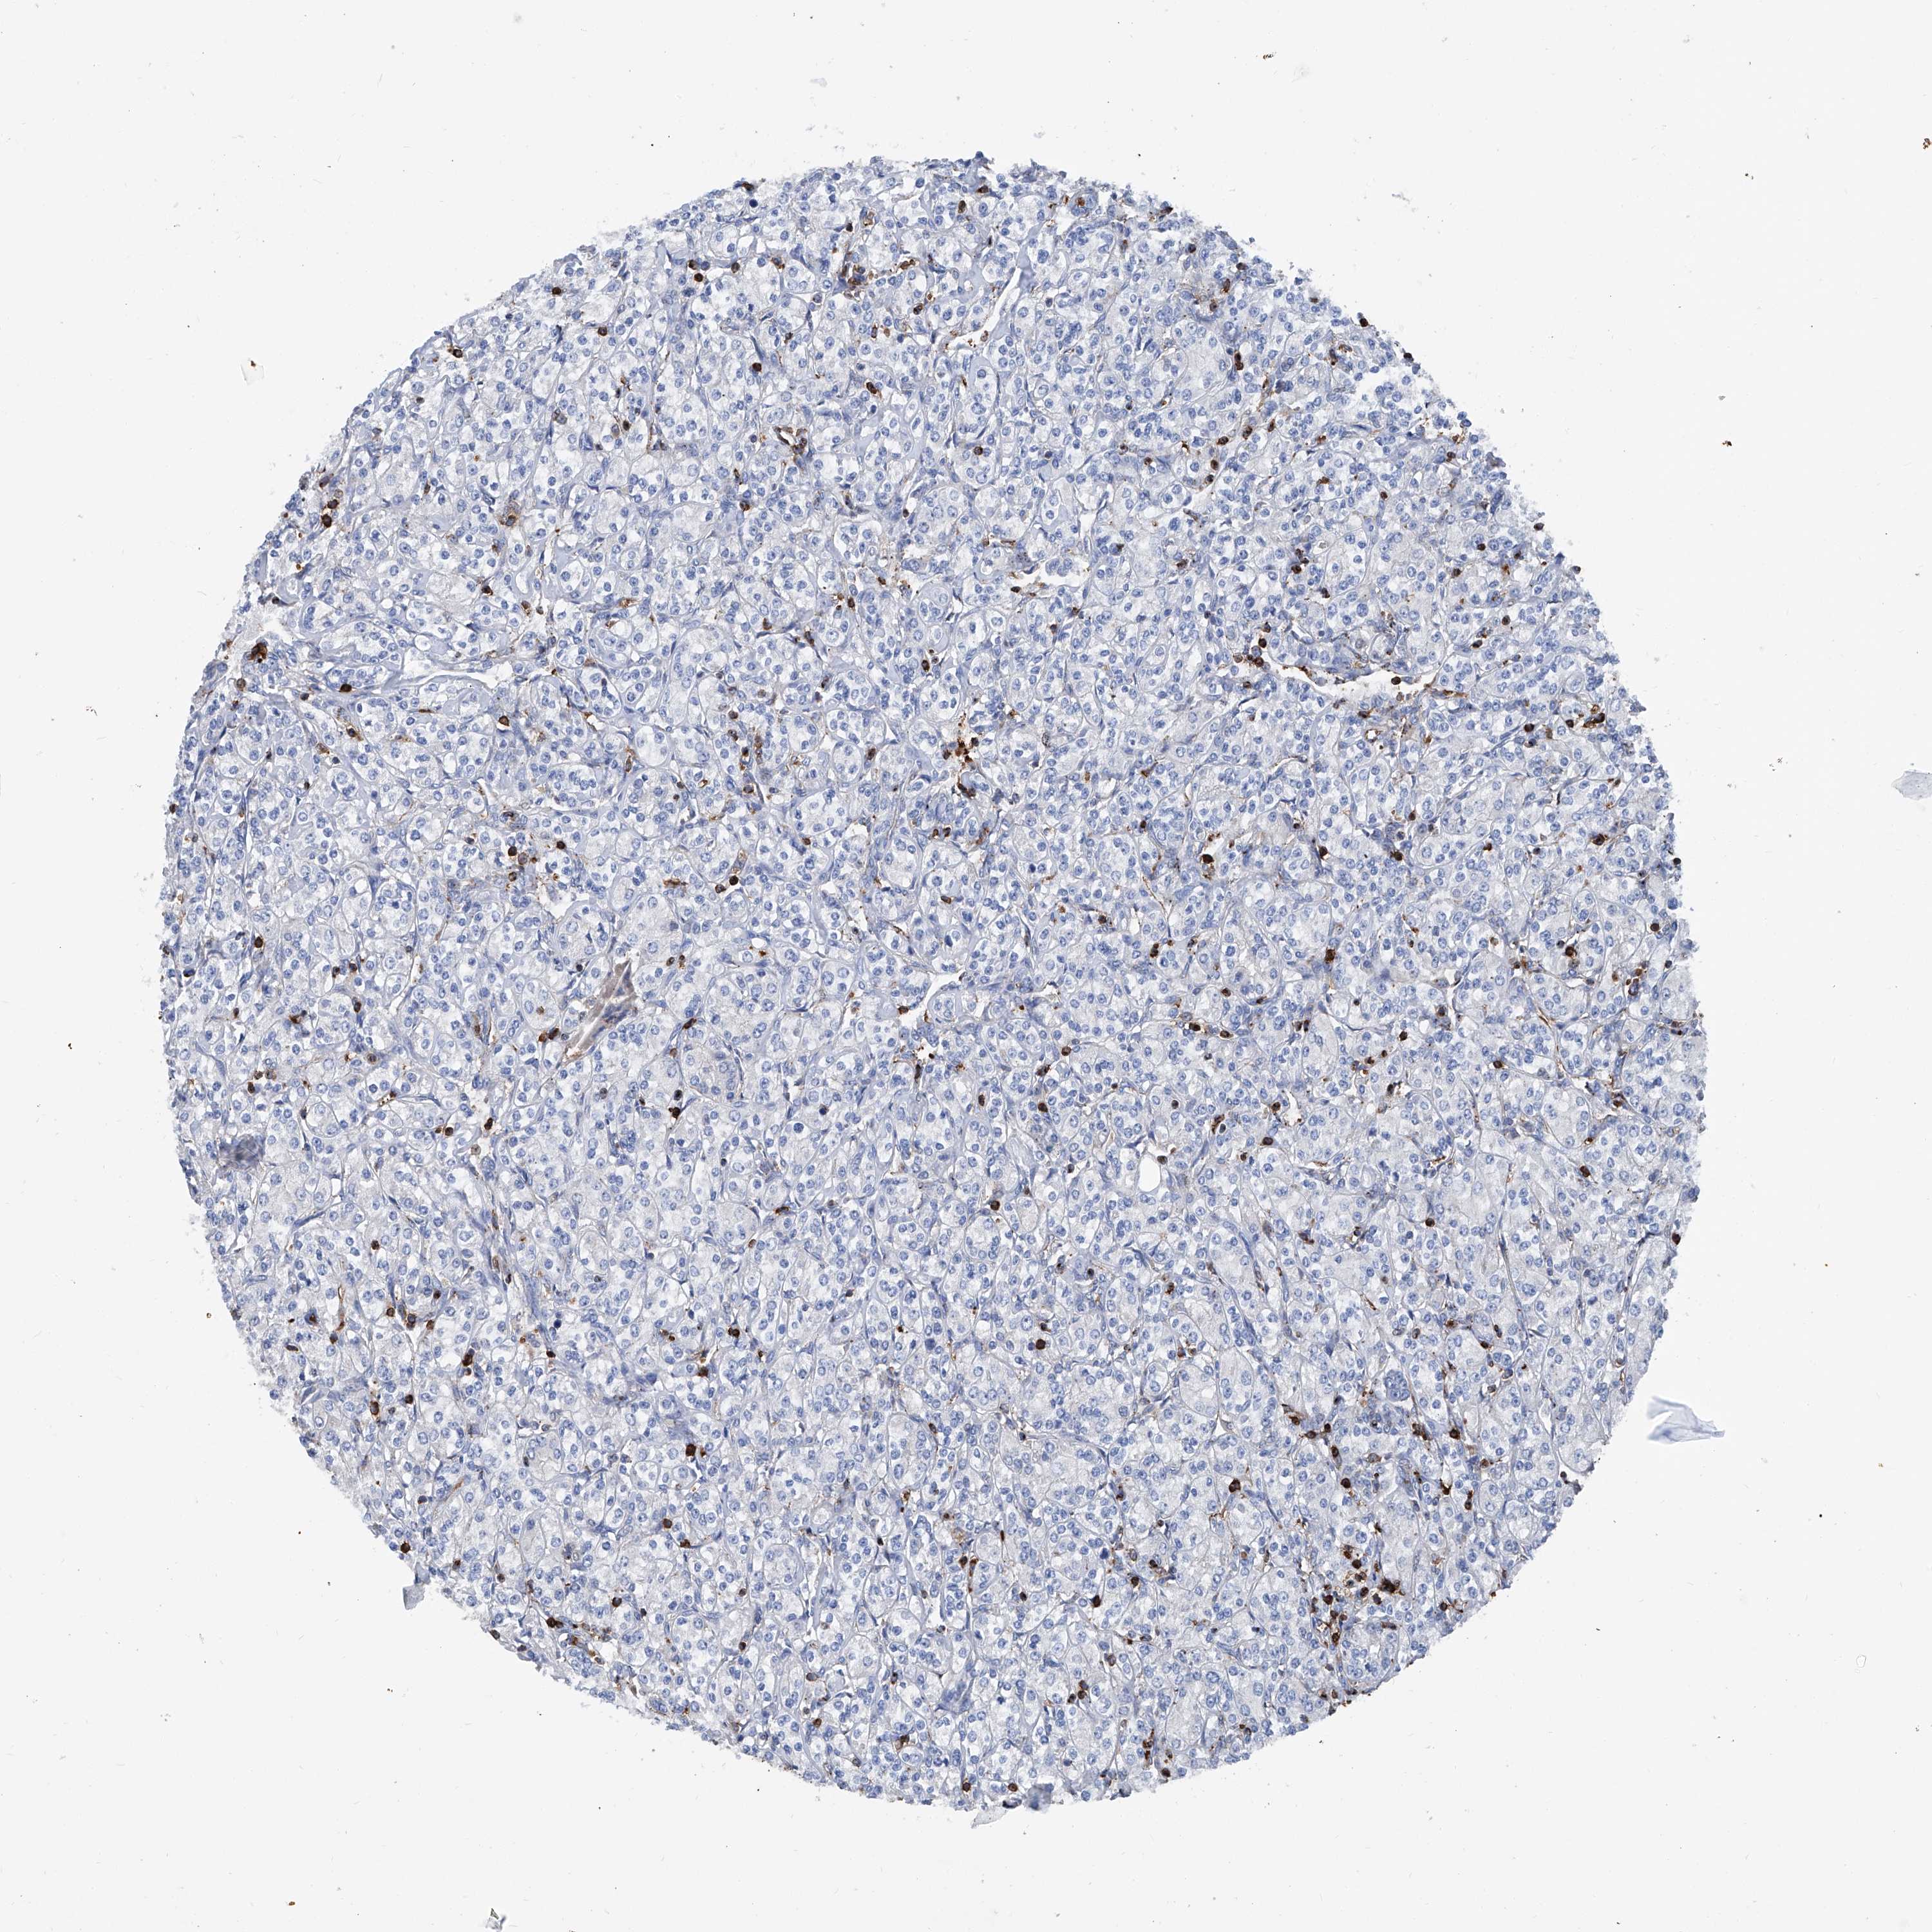

KIDNEY RENAL CLEAR CELL CARCINOMA (TCGA) - Interactive survival scatter ploti

The Survival Scatter plot shows the clinical status (i.e. dead or alive) for all individuals in the patient cohort, based on the same data that underlies the corresponding Kaplan-Meier plots. Patients that are alive at last time for follow-up are shown in blue and patients who have died during the study are shown in red.

The x-axis shows the expression levels (FPKM) of the investigated gene in the tumor tissue at the time of diagnosis. The y-axis shows the follow-up time after diagnosis (years). Both axes are complimented with kernel density curves demonstrating the data density over the axes. The top density plot shows the expression levels (FPKM) distribution among dead (red) and alive patients (blue). The right density plot shows the data density of the survived years of dead patients with high and low expression levels respectively, stratified using the cutoff indicated by the vertical dashed line through the Survival Scatter plot. This cutoff is automatically defined based on the FPKM cutoff that minimizes the p-score. The cutoff can be changed by dragging the vertical line or by entering a cutoff value in the square labeled "Current cut-off".

Under the Survival Scatter plot the p-score landscape (black curve; left axis) is shown together with dead median separation (red curve; right axis). Dead median separation is the difference in median mRNA expression between patients who have died with high and low expression, respectively. It is calculated as follows: median FPKM expression of dead patients with high expression - median FPKM expression of dead patients with low expression. This is intended to aid the user in visually exploring custom cutoffs and the associated p-scores and dead median separation.

Individual patient data is displayed and can be filtered by clicking on one or more of the category buttons on the top of the page. Categories describing expression level and patient information include: high, low, alive, dead, female, male and tumor stages. The scale of the x-axis can be toggled between linear and log-scale by clicking on the "x log" button. Mouse-over function shows TCGA ID, patient information and mRNA expression (FPKM) for each patient.

& Survival analysisi

Kaplan-Meier plots summarize results from analysis of correlation between mRNA expression level and patient survival. Patients were divided based on level of expression into one of the two groups "low" (under cut off) or "high" (over cut off). X-axis shows time for survival (years) and y-axis shows the probability of survival, where 1.0 corresponds to 100 percent.

ZNF484 is validated prognostic, high expression is favorable in Kidney Renal Clear Cell Carcinoma (TCGA)

: 3.17

Average pTPM 2.4

Number of samples 521